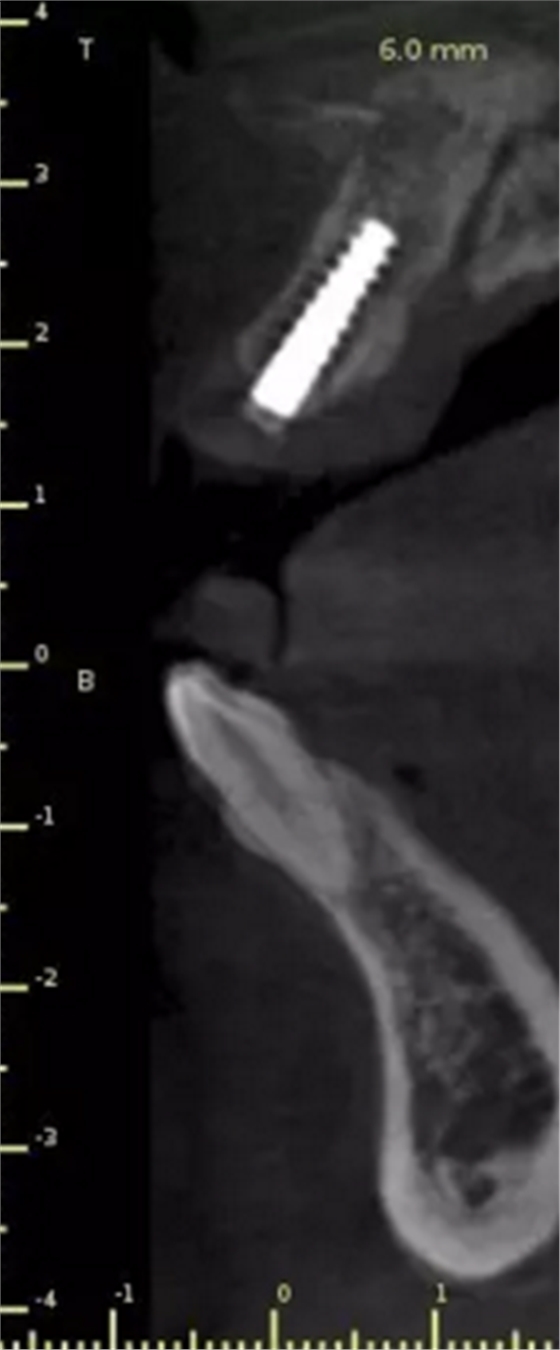

1.術(shù)前CT

2.術(shù)前植體設(shè)計(jì)

術(shù)后CT